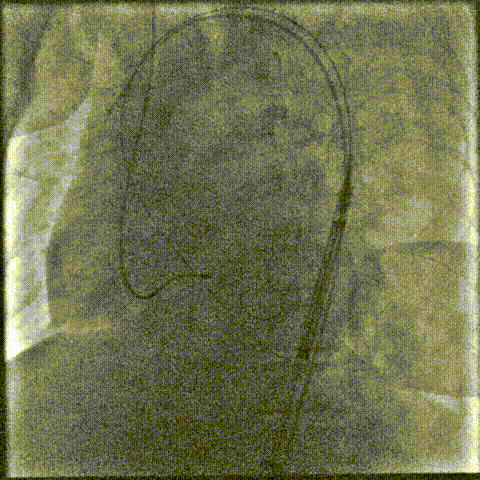

2.主动脉根部造影

7.gif